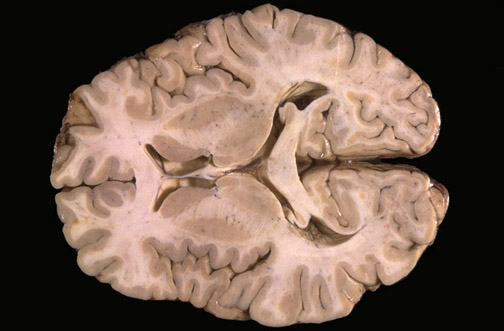

| Identify the following regions of the brain on transverse section in the image above: Head of the Caudate Nucleus - Putamen - Fimbria of Hippocampus & Fornix - Fornix - Anterior Nucleus of Thalamus - Genu of Corpus Callosum - Splenium of Corpus Callosum - Insular Cortex - Calcarine Cortex |